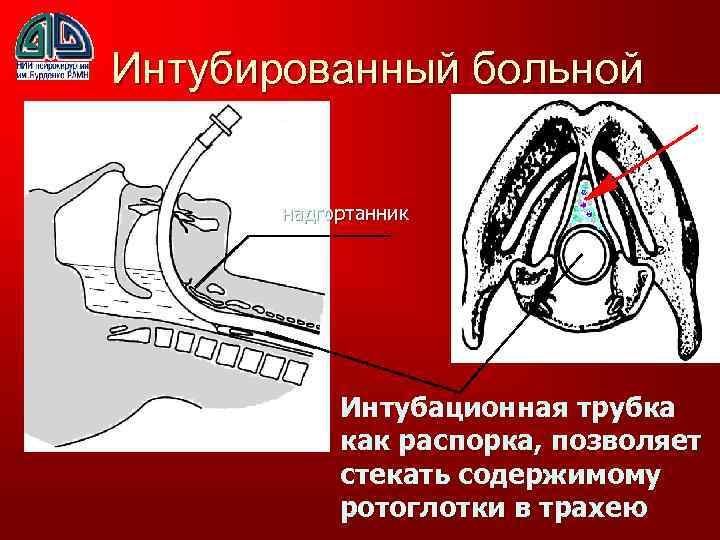

Интубированный больной надгортанник Интубационная трубка как распорка, позволяет стекать содержимому ротоглотки в трахею

Интубированный больной надгортанник Интубационная трубка как распорка, позволяет стекать содержимому ротоглотки в трахею

Интубация или трахеостомия надгортанник Интубационная трубка блокирует голосовые складки и надгортанник

Интубация или трахеостомия надгортанник Интубационная трубка блокирует голосовые складки и надгортанник